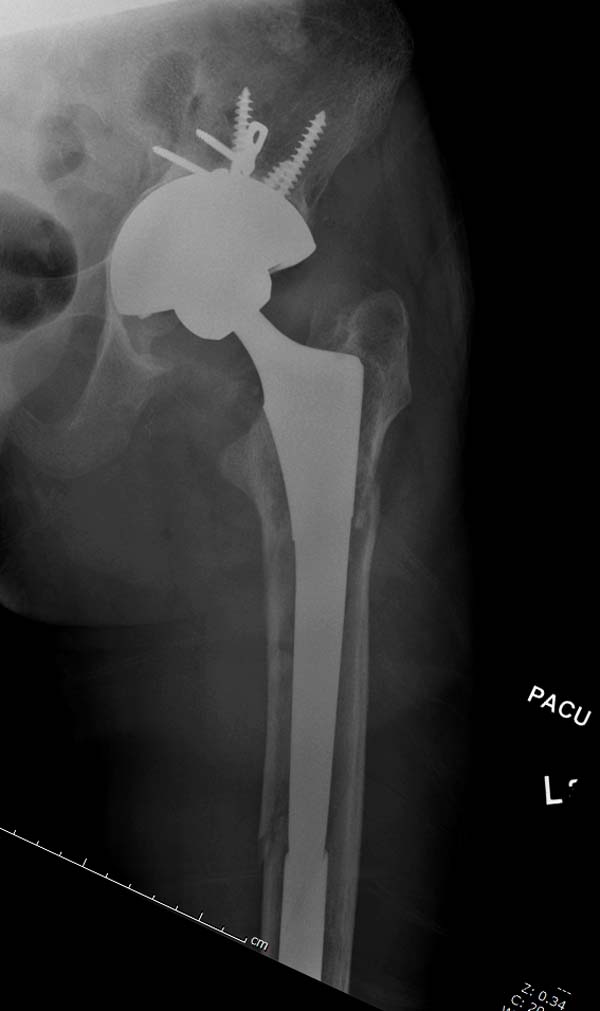

остаться до конца лечения, начал изучать язык... Для облегчения

транспортировки на второй день после поступления правая сторона была

фиксирована ретроградным гвоздем.

Теперь по серьезному. Учитывая качество кости и низкий гемоглобин,

периодический гемодиализ и воодушевленный результатом выступлении

Челнокова, вместо пластины решил попробовать гвоздь. Но жесткие FDА

Гвоздь из ретроградного гвоздя DePuy в 15 мм получился немного тоньше,

чем у Российских коллег.

А так вроде первый американский опыт прошел удачно. У больного низкий

гемоглобин, который подправили во время операции переливанием крови.

надеюсь, контрагированные мышцы сохранит длину конечности. Контрольный

снимок показал устойчивую фиксацию.